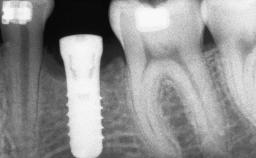

Replacement of Multiple Teeth in a Partially Dentate Posterior Mandible with a Fixed Dental Prosthesis Using a Flapless Approach

An 80-year-old female patient was referred to clinic for rehabilitation of her dentition. The patient’s medical history revealed no significant findings that would preclude routine dental and oral surgical procedures. She reported no drug allergies and was currently taking no prescription medications.

# of Teeth 4

# of Implants 4

Placement Protocol Early or late implant placement

Bone Volume Horizontally and vertically sufficient